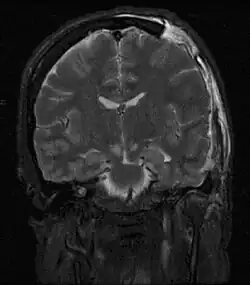

Een van de meest schadelijke gevolgen van traumatisch hersenletsel, direct geassocieerd met een slechte prognose, is een verhoogde intracraniële druk. Verhoogde intracraniële druk kan blijvende schade veroorzaken.[3] Ernstig verhoogde druk is vaak dodelijk wanneer deze lang aanhoudt, al kunnen kinderen hogere druk vaak langer weerstaan. Een toename in de druk wordt meestal veroorzaakt door hoofdletsel dat een intracerebraal hematoom of oedeem veroorzaakt, hersenweefsel samendrukt, hersenstructuren verplaatst, bijdraagt aan hydrocefalus, hersenkneuzing veroorzaakt, of de bloedtoevoer aan de hersenen beperkt.[4] Het kan een verlaagde hartslag veroorzaken.[5]